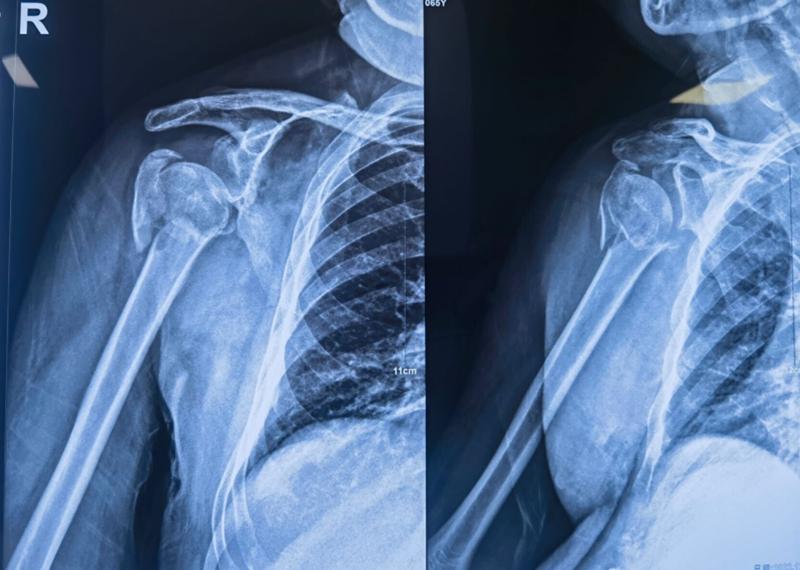

Xxx,男,65岁,右肱骨近端四部分骨折一周。

图16 术前X片

肩前外侧劈三角肌入路,三角肌前束和中间束肌肉间隙进入,双套固定技术加强固定。

图17 术中

术中C-臂检测:

图18 肱骨距螺钉固定确切

术中大幅度肩关节屈伸与外展内收活动,提示骨折坚强固定。

图19 术后X片